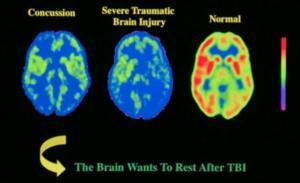

8. When we look at three brains: one uninjured, one with a concussion, and one with a severe TBI (Traumatic Brain Injury), we notice obvious differences, particularly in these areas mentioned, above:

image from http://www.vitamindwiki.com

To orient you: top of photos = forehead/frontal areas of brain. Look at the differences in these three scans in that area, particularly. Startling, huh?

I could be wrong, here, but I think these scans are oriented in opposite ways from those in #8. Top = back/neck, or the occipital lobe area. Look, therefore, at the bottoms of these scans to see how the frontal areas are affected.

Remember, though: most concussion injuries and symptoms do not show up on MRIs, CAT scans or X-rays, even when taken on the same day as the injury, much less those taken weeks or months later. Functional MRIs and PET scans are slightly better, but many effects are just not all that easy to visualize with the technology currently available.